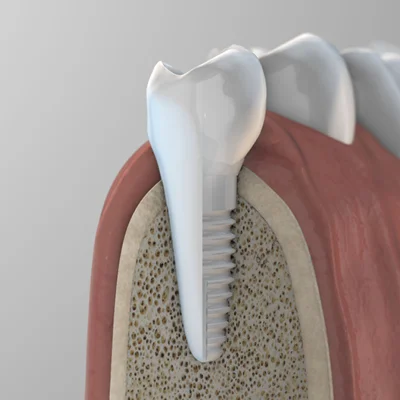

รากฟันเทียมเซรามิก (Ceramic Dental Implants) เป็นเทคโนโลยีการปลูกรากฟันเทียมที่ใช้สำหรับทดแทนรากฟันที่ถูกถอนออกไป โดยวัสดุหลักที่ใช้ผลิตคือ เซอร์โคเนีย (Zirconia) ซึ่งเป็นเซรามิกชนิดหนึ่งที่มีคุณสมบัติโดดเด่นในด้านความแข็งแรงทนทานสูง เทียบเท่ากับโลหะ แต่มีสีขาวเหมือนฟันธรรมชาติ ทำให้เป็นทางเลือกที่ได้รับความสนใจอย่างมากในวงการทันตกรรมความงามและการแพทย์องค์รวม (Holistic Dentistry) เนื่องจากเป็นวัสดุที่ไร้โลหะ 100% (Metal-free)

ในอดีต รากเทียมที่ใช้กันอย่างแพร่หลายคือรากเทียมที่ทำจากไทเทเนียม ซึ่งมีความแข็งแรงและใช้งานได้ดีเยี่ยมมาโดยตลอด แต่ในบางกรณีก็อาจมีข้อกังวลเรื่องสีเทาของโลหะที่อาจจะโผล่ให้เห็นบริเวณขอบเหงือก หรือในผู้ป่วยบางรายที่กังวลเรื่องการแพ้โลหะ

- วัสดุ: รากเทียมเซรามิกทำจาก เซอร์โคเนีย ซึ่งเป็นเซรามิกชนิดหนึ่ง มีสีขาวทั้งหมด ไม่มีส่วนประกอบของโลหะ ส่วนรากเทียมทั่วไปทำจาก ไทเทเนียม ซึ่งเป็นโลหะที่มีสีเงิน

- ความสวยงาม: เนื่องจากมีสีขาวเหมือนฟันธรรมชาติ รากเทียมเซรามิก จึงไม่เกิดเงาดำหรือสีเทาบริเวณขอบเหงือกเหมือนกับรากเทียมไทเทเนียม ทำให้เหมาะอย่างยิ่งสำหรับการปลูกรากฟันหน้า